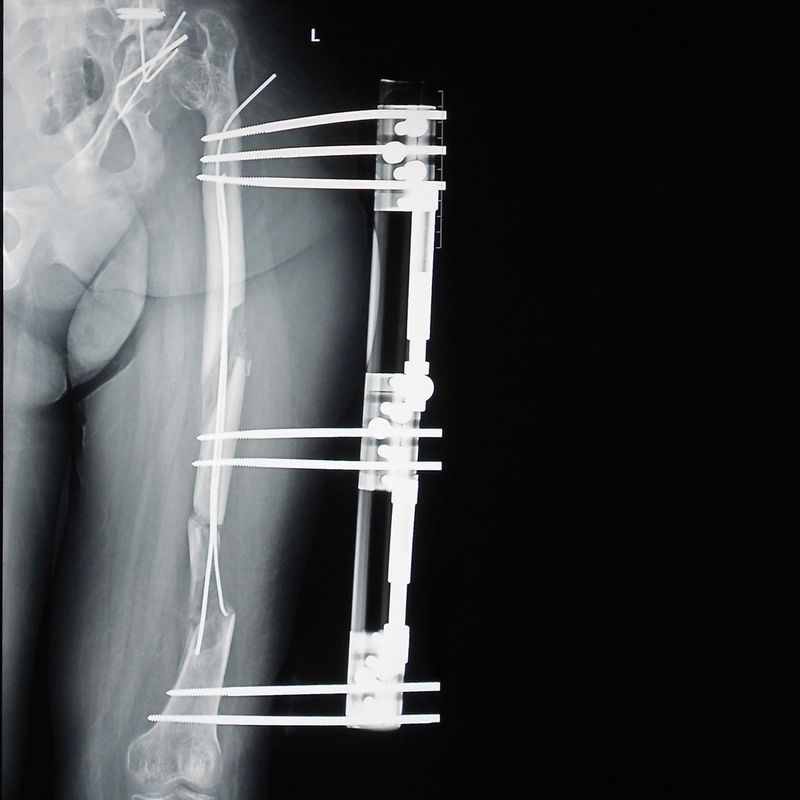

Aici, cazul Amirei a fost prezentat pe larg, alaturi de dovezi ale erorilor medicale facute de Burnei de-a lungul celor 18 ani in care a tratat-o pe tanara. Amira a suportat 11 interventii chirurgicale, prima fiind la varsta de un an, dupa o banala luxatie de sold.